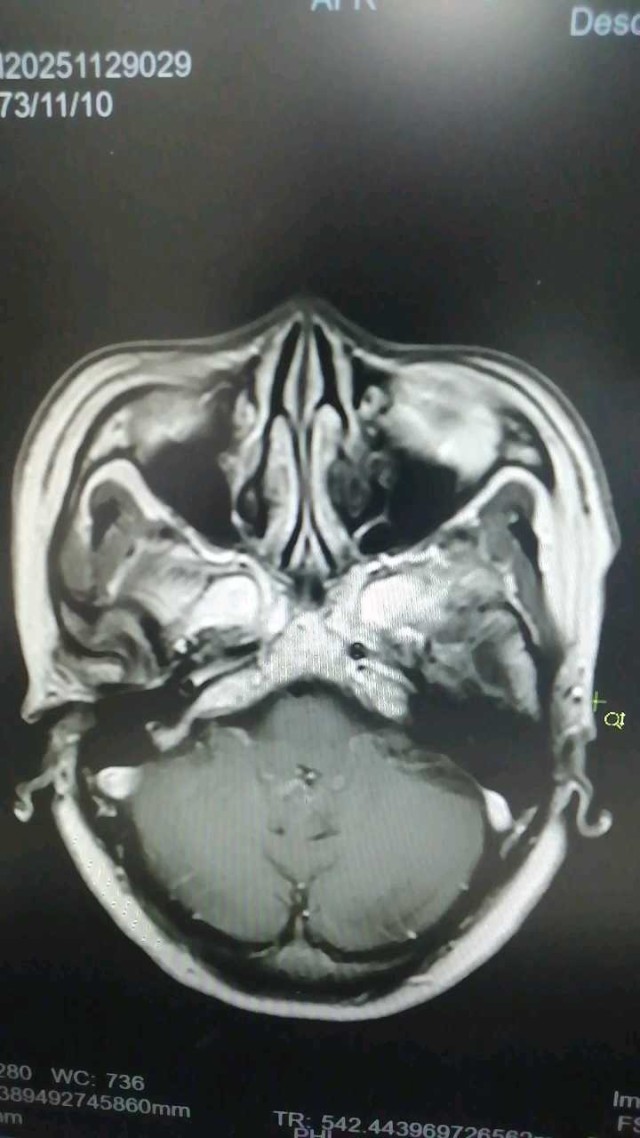

白某某,女性,73岁,2024年01月09日入院。主诉:进展性双下肢无力15天现病史:15天前(12月26日7:00)无明显诱因突发双下肢无力,可缓慢行走,(12月26日9:00)渐进行性加重,双下肢抬离床面困难,不能行走,伴双下肢感觉障碍,小便困难及大便失禁,持续性,无头痛、眩晕、恶心、呕吐,无意识丧失、肢体抽搐、口吐白沫、双眼凝视,偶有口角流涎,无言语含糊、饮水呛咳、吞咽困难。立即就诊于当地县人民医院,因起病急,症状重,病情进展快,双下肢感觉障碍,尿便障碍,短时间内诊断困难,当天转诊于某大学附属医院神经外科,按双下肢无力待查:胸髓缺血诊治后好转,双下肢较前有力,可借助外物缓慢挪步,行走不稳

coverplay

病例 · 319 浏览 · 4 讨论